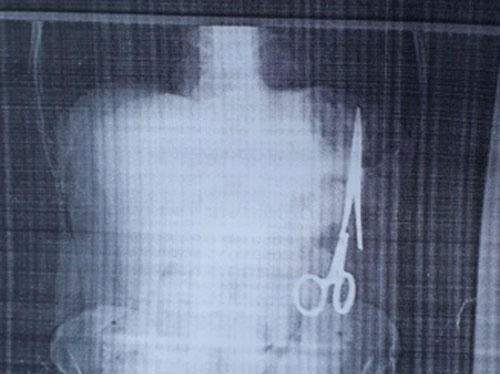

Đau nhói ở bụng sau một lần việc quá sức, ông Nhật vào Bệnh viện Gang thép Thái Nguyên khám.Kết quả siêu âm ngày 25/12 cho thấy trong ổ bụng của ông có một chiếc kéo dài khoảng 15 cm, được cho là chiếc panh chuyên dùng để mổ của ngành y. 2 ngày sau ông đến siêu âm tại Bệnh viện đa khoa Bắc Kạn, kết quả tương tự.

Chiếc kéo được cho là đã nằm trong bụng bệnh nhân 18 năm. Ảnh: TTXVN. |

Theo ông Nhật, trừ lần phẫu thuật cách đây 18 năm, ông chưa phải vào viện mổ lần nào nữa. Khi đó là tháng 6/1998, ông bị tai nạn giao thông khiến ghi đông xe đâm vào mạng sườn, được chuyển từ bệnh viện huyện ra bệnh viện đa khoa tỉnh và được chỉ định phẫu thuật. Sau mổ, ông vẫn ăn uống và sinh hoạt bình thường.